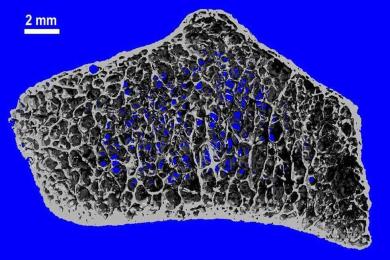

علوم تغییرات خاموش در مغز استخوان ممکن است علامت اولیه سرطان خون باشد التهاب در محیط مغز استخوان که سلولهای ویژهای به نام سلولهای استرومال مزانشیمی التهابی آنها را ایجاد میکنند، نیرویی کلیدی در نخستین مراحل بیماریهای خونی است مصرف روزانه زنجبیل چه اثری بر فشار خون دارد؟ نشانههای سرطان مرگباری که زنان را بیشتر تهدید میکند چهار توصیه متخصص قلب برای کاهش خطر حمله قلبی